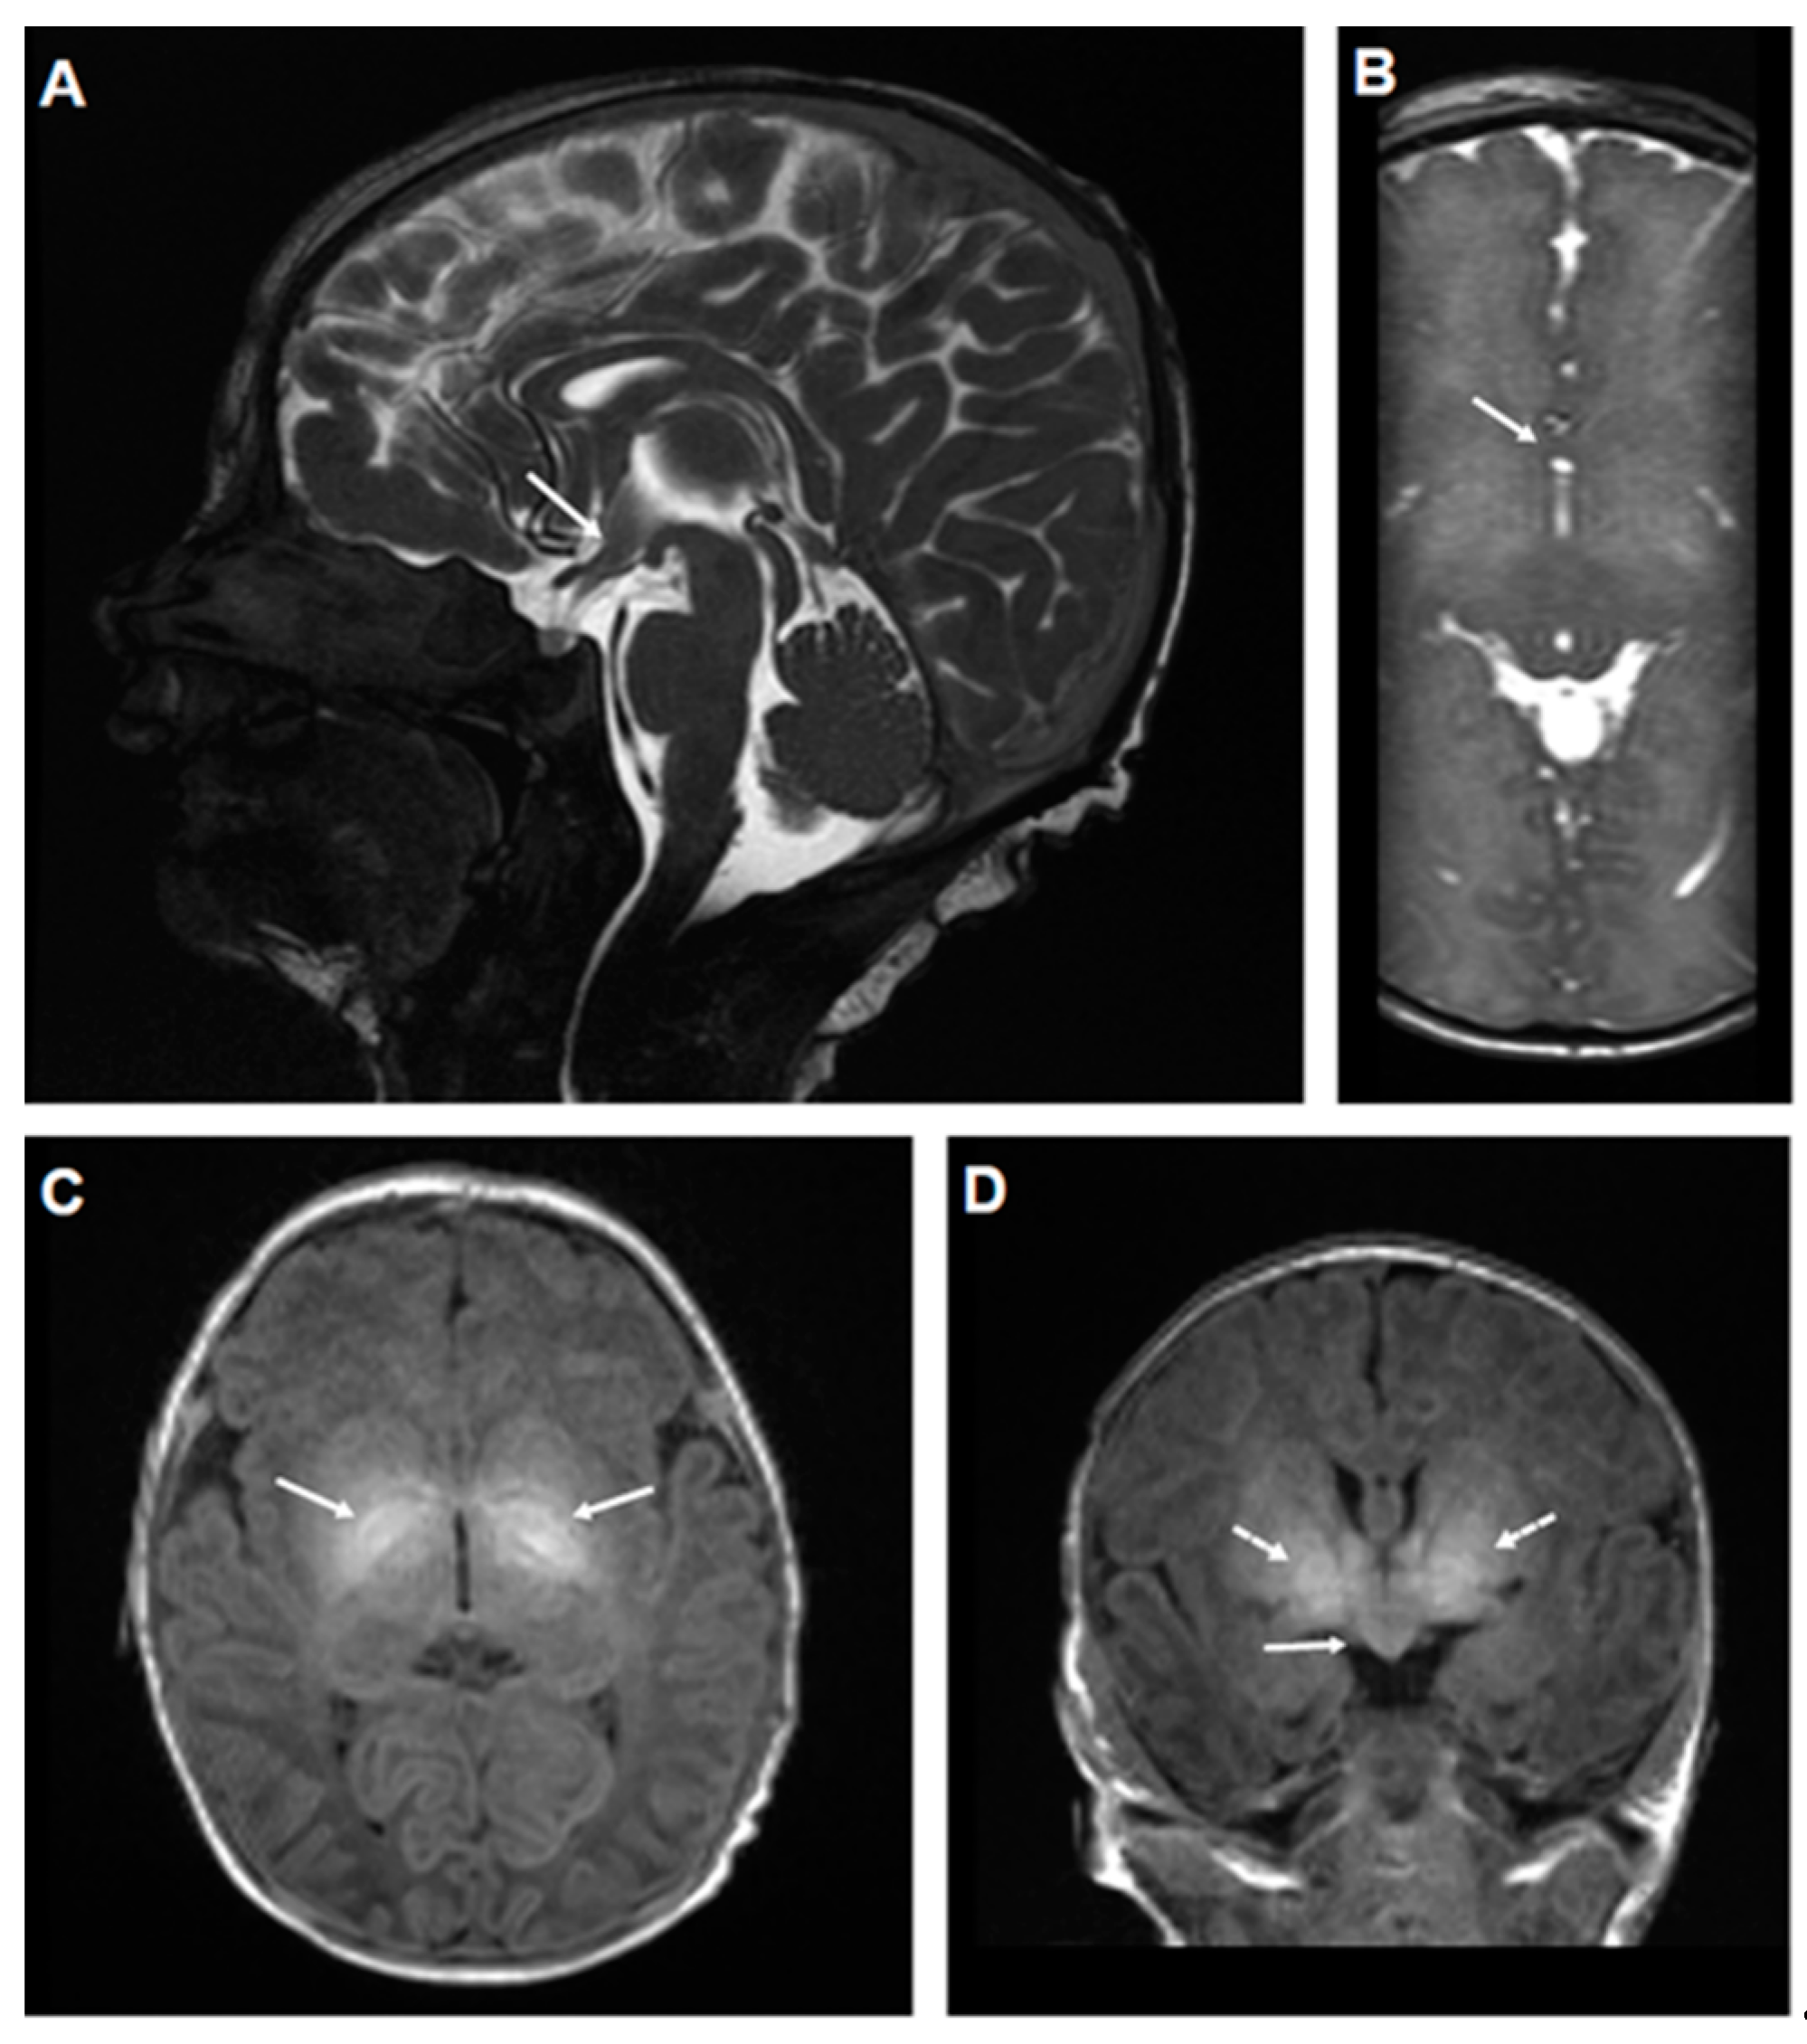

2.1. Genetic and Clinical Description of the Proband